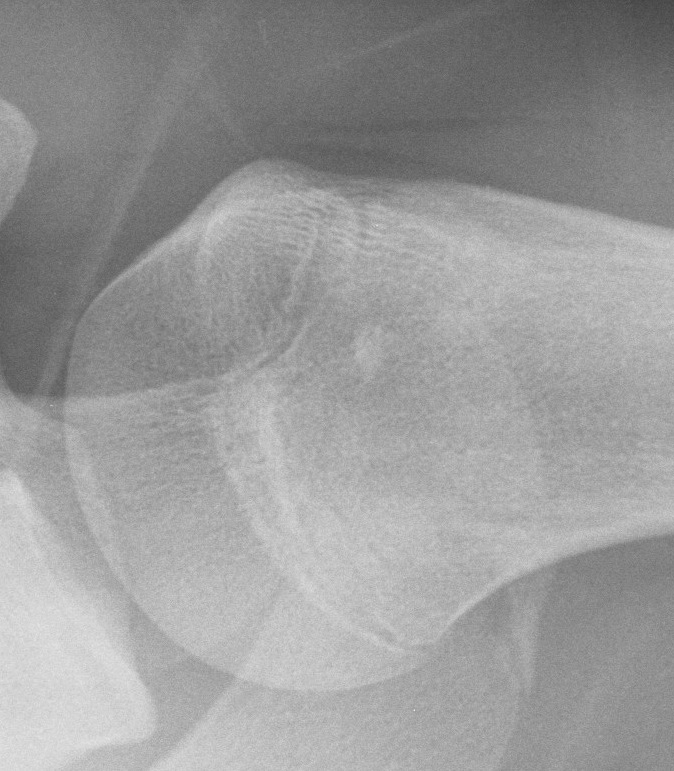

X-ray

Sharply-circumscribed cortical densities

- round or oval in shape with smooth, regular borders

- narrow zone of transition from lesion to cancellous bone

- no evident reaction to the process

Usually < 1 cm in diameter